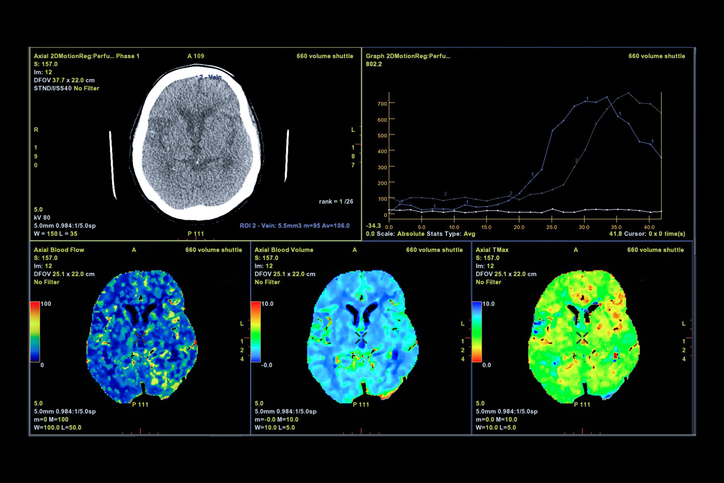

Genau hier kommen Hypnose und Neuroplastizität zusammen – und zwar messbar. Im Trancezustand verändert sich deine Gehirnwellenaktivität hin zu Alpha- und Theta-Frequenzen. Auf neurologischer Ebene passiert etwas Bemerkenswertes:

Forscher um Heidi Jiang von der Northwestern University in Chicago bezeichnen Hypnose als „die älteste Form westlicher Psychotherapie" und beschreiben sie als ein effektives Mittel, um die Art und Weise zu verändern, wie wir unser Gehirn benutzen. Mithilfe moderner bildgebender Verfahren – konkret dem fMRT, der funktionellen Magnetresonanztomographie – konnten Wissenschaftler erstmals genau beobachten, was im Gehirn während einer Trance passiert. Das Ergebnis:

Es sind drei klar messbare Veränderungen, die den Trancezustand charakterisieren.

Erstens sinkt die Aktivität im sogenannten Salienz-Netzwerk,

genauer gesagt im dorsalen anterioren Gyrus cinguli.

Dieses Netzwerk ist normalerweise dafür verantwortlich, unsere Aufmerksamkeit auf wichtige äußere Reize zu lenken.

Wird es abgeschwächt – wie in Hypnose – verlagert sich der Fokus von außen nach innen. Du bist ganz bei dir, bei deinen inneren Bildern, Empfindungen und Vorstellungen.

Zweitens verändert sich die Verbindung zwischen dem präfrontalen Kortex und der Inselrinde – jenem Bereich, der für Körperwahrnehmung und Emotionen zuständig ist. Diese Verbindung wird in Hypnose verstärkt, was erklärt, warum Suggestionen nicht nur mental, sondern auch körperlich wirken können.

Drittens wird das sogenannte Default Mode Network – das Netzwerk, das aktiv ist, wenn wir grübeln, tagträumen oder uns gedanklich im Kreis drehen – deutlich heruntergefahren. Du bist klar fokussiert, ganz im Moment, und frei von ablenkenden Gedanken oder innerer Kritik.